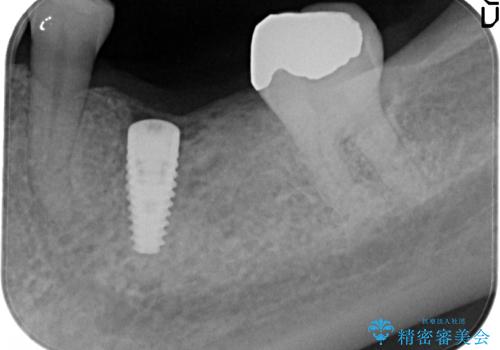

- Ⅲ度の分岐部病変をきたした第1大臼歯を抜去、待時しインプラントによる咬合回復を計画した。

インプラントの種類:strauman SLActive

かぶせ物の種類:Bellezza screw retain